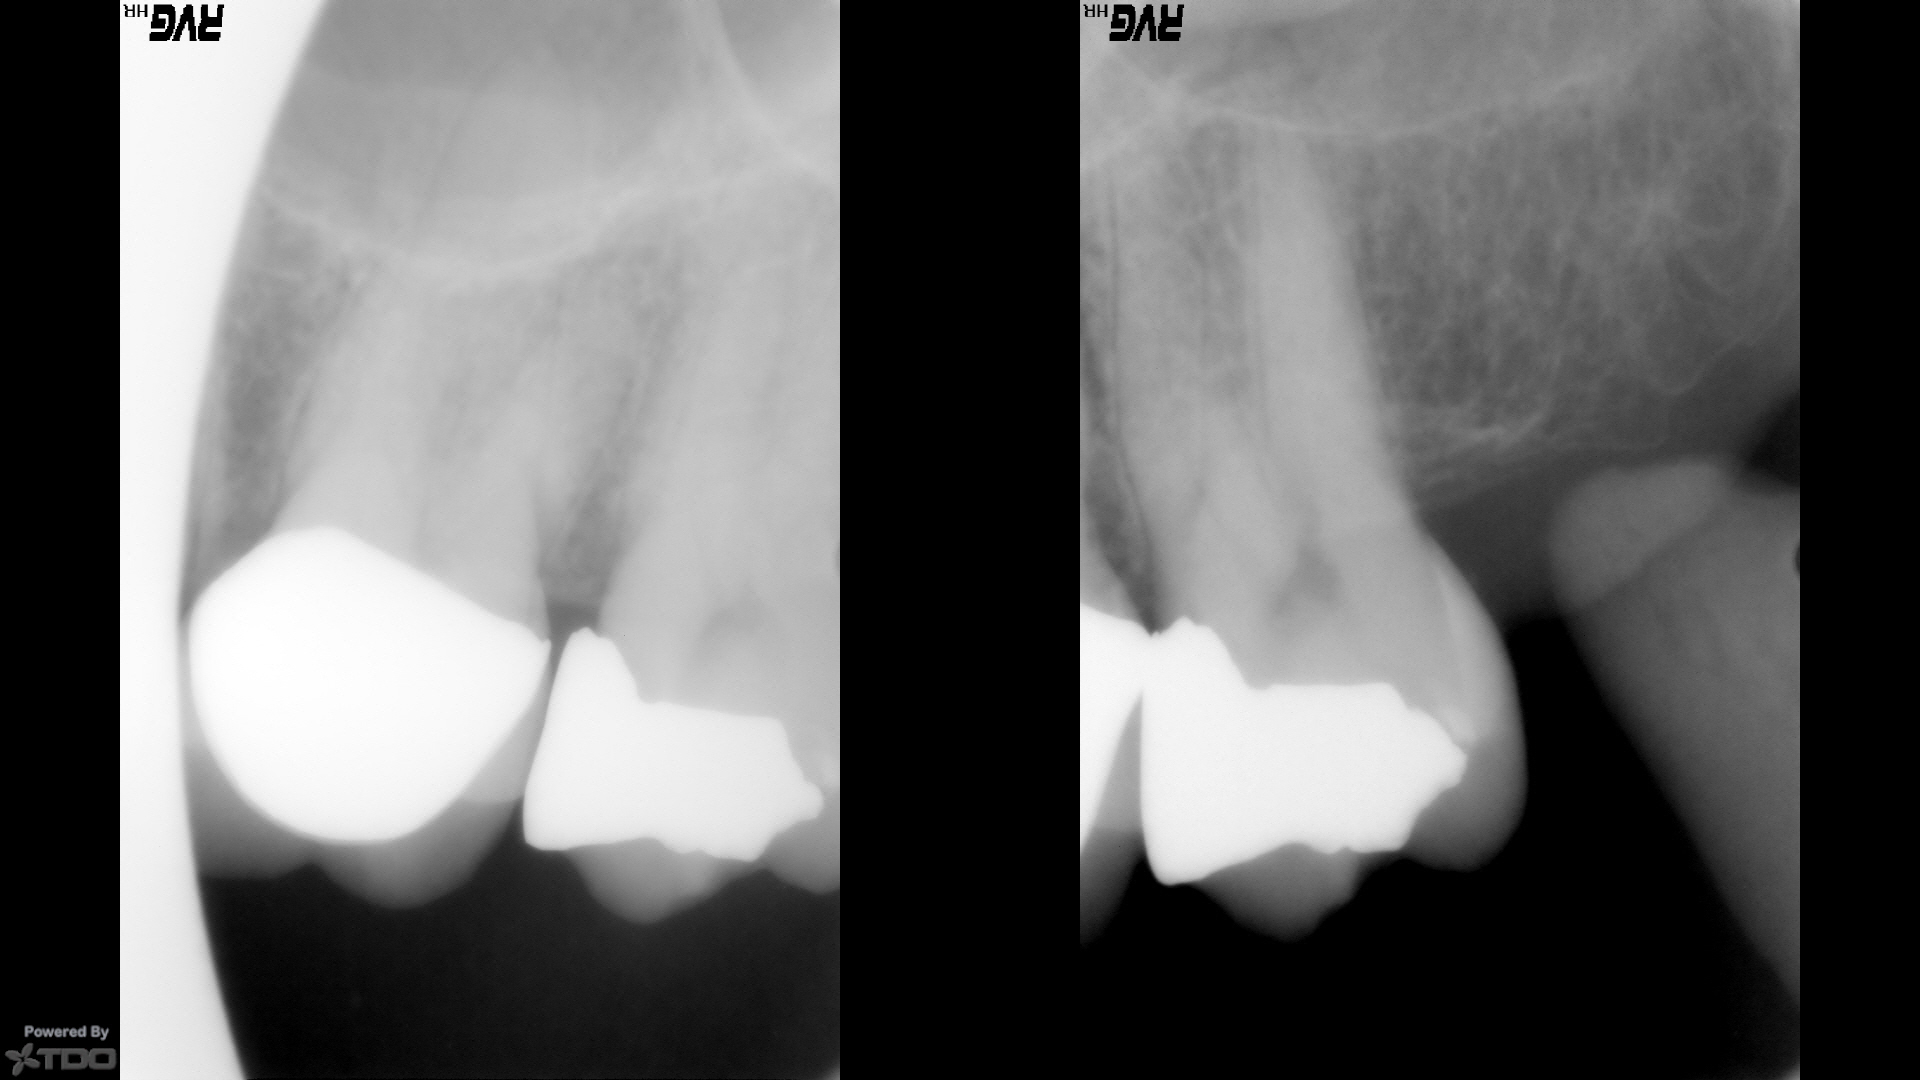

UL sensitive to hot/cold and aches for two months. Not keeping her up at night. Pressure sensitive to chewing, dull ache. No pain meds. Had large filling placed one year ago on #15. See pt. chart for test results.  Crack on number #15, large overhang.